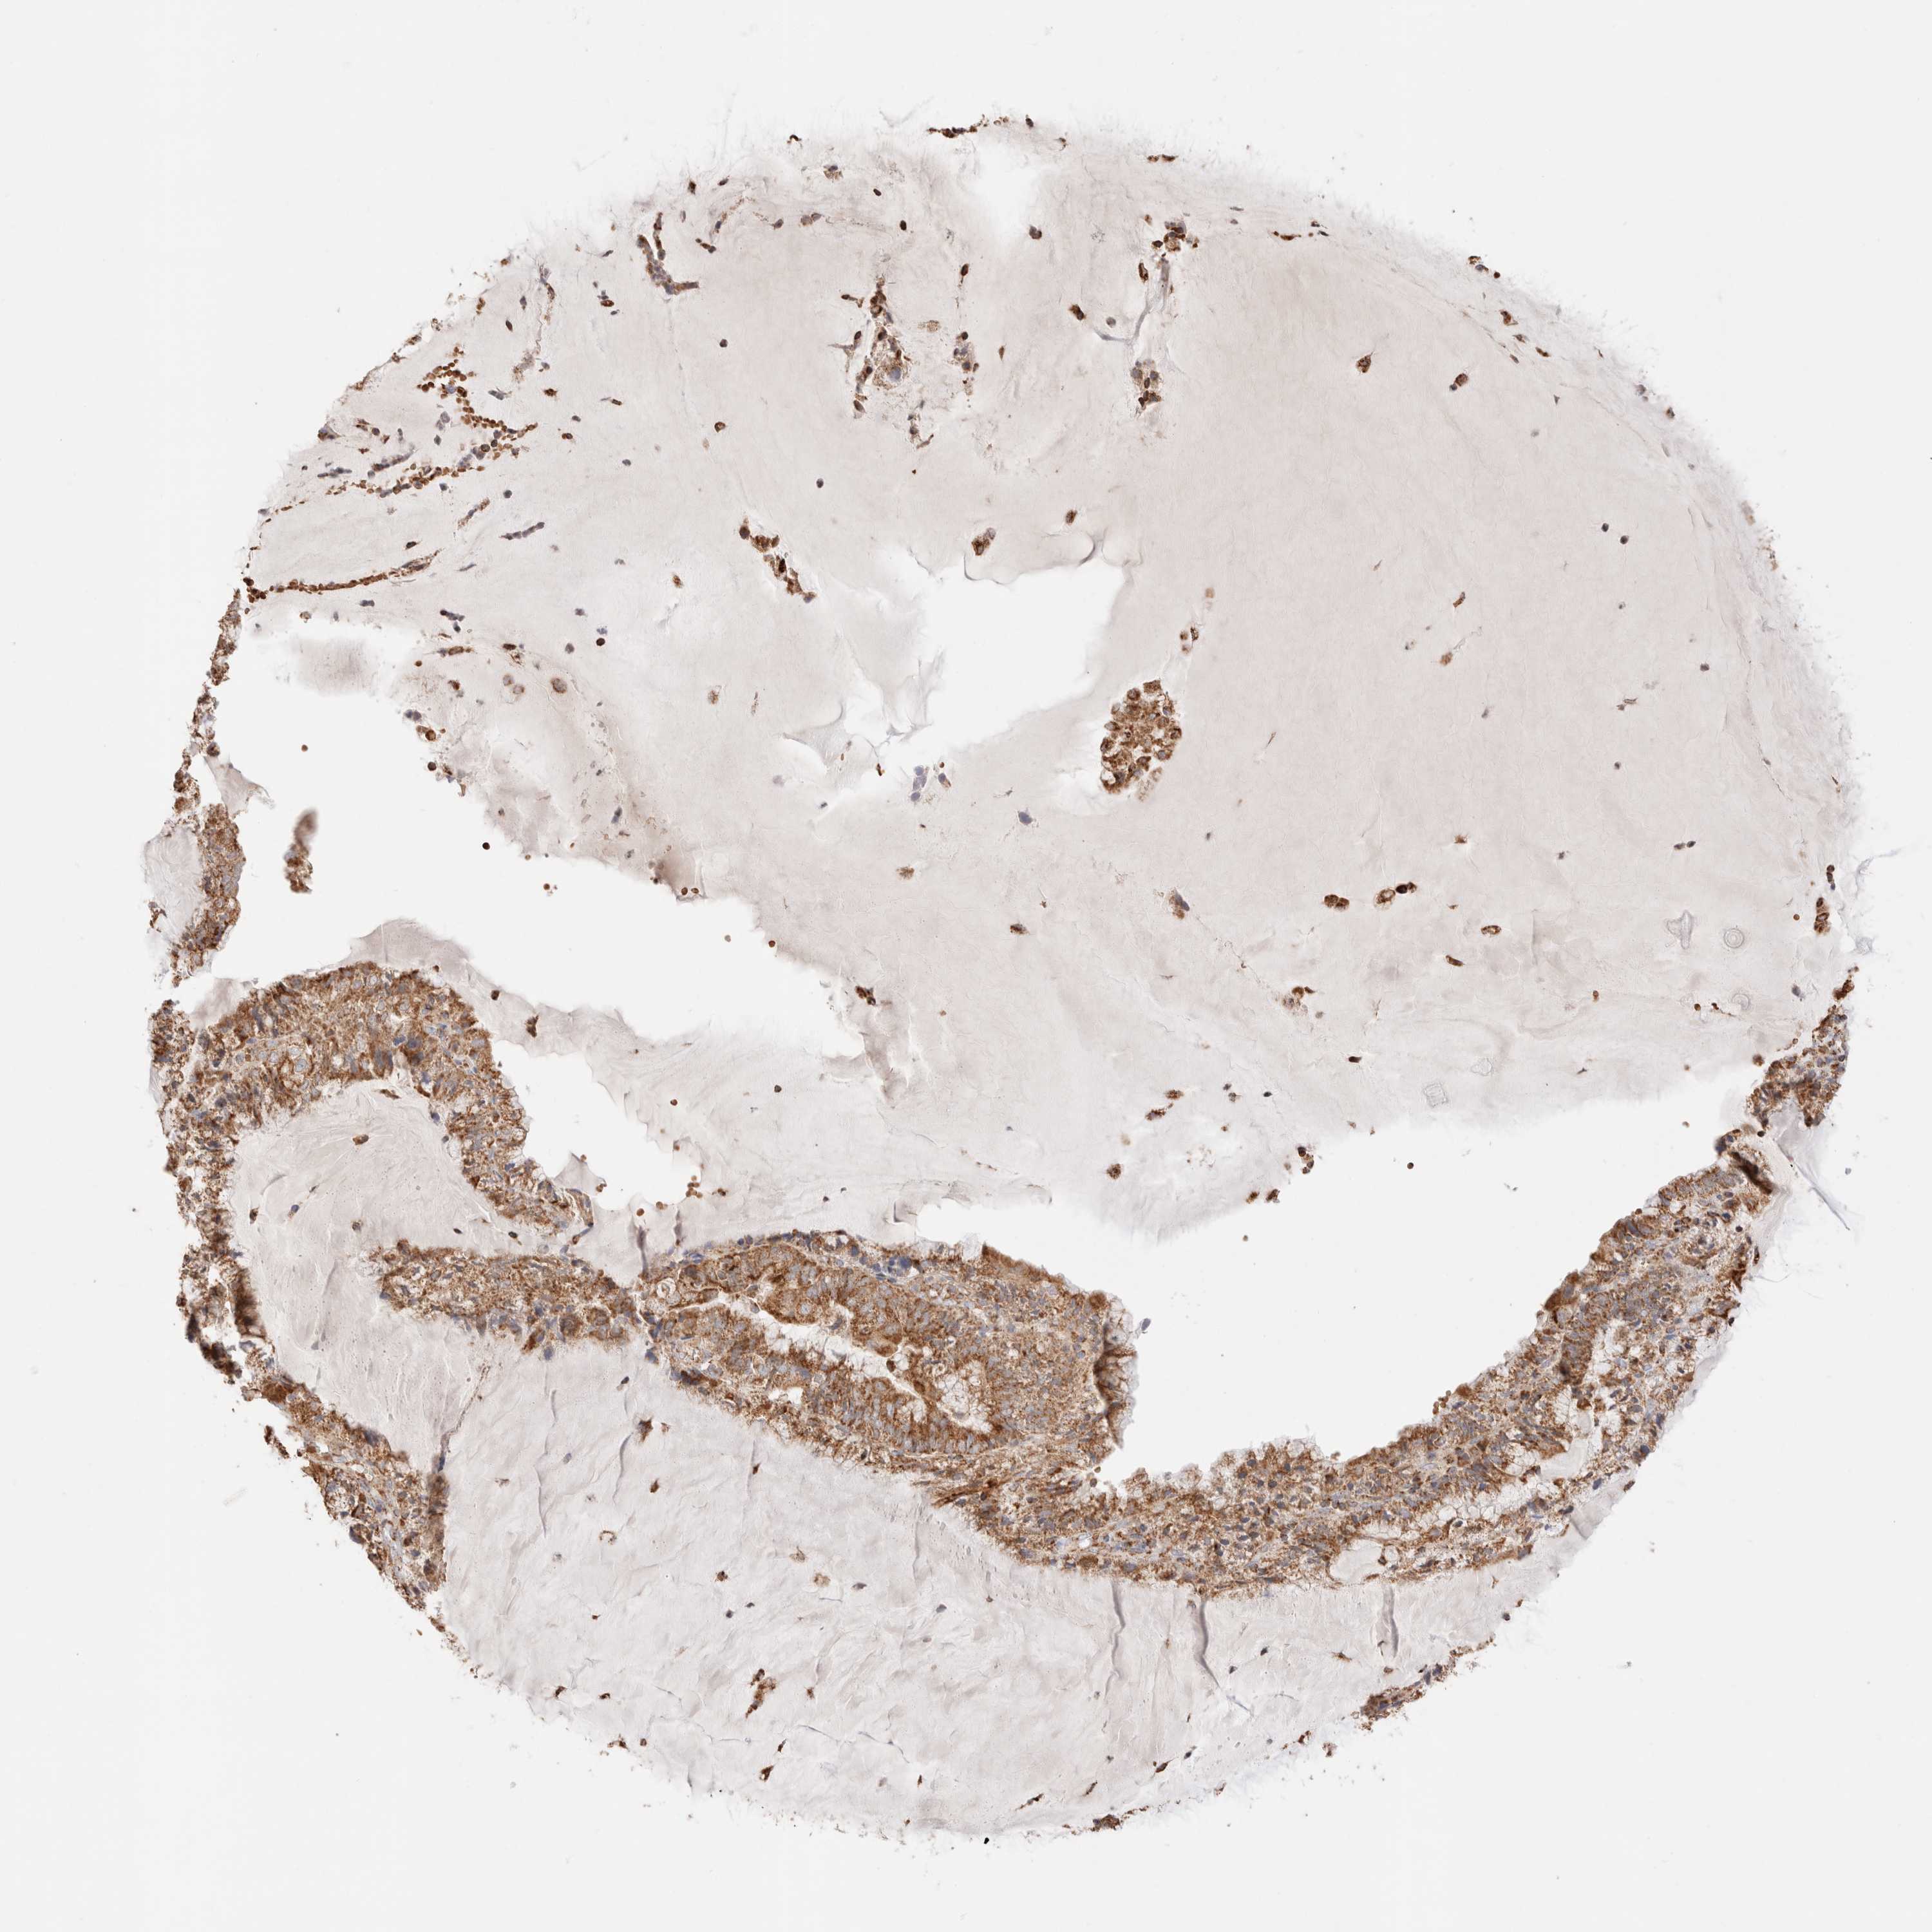

ENDOMETRIAL CANCER - Protein expressioni

A mouse-over function shows sample information and annotation data. Click on an image to view it in a full screen mode. Samples can be filtered based on level of antibody staining by selecting one or several of the following categories: high, medium, low and not detected. The assay and annotation is described here.

Note that samples used for immunohistochemistry by the Human Protein Atlas do not correspond to samples in the TCGA dataset.

Antibody stainingi

Antibody staining in the annotated cell types in the current human tissue is reported as not detected, low, medium, or high, based on conventional immunohistochemistry profiling in selected tissues. This score is based on the combination of the staining intensity and fraction of stained cells.

Each image is clickable and will lead to virtual microscopy that enables deeper exploration of all samples and also displays staining intensity scores, fraction scores and subcellular localization as well as patient and tissue information for each sample.

Antibody HPA027019

Staining

High

Medium

Low

Not detected

Intensity

Strong

Moderate

Weak

Negative

Quantity

>75%

75%-25%

<25%

None

Location

Nuclear

Cytoplasmic/membranous

Cytoplasmic/membranous,nuclear

Adenocarcinoma, NOS

Adenocarcinoma, metastatic, NOS